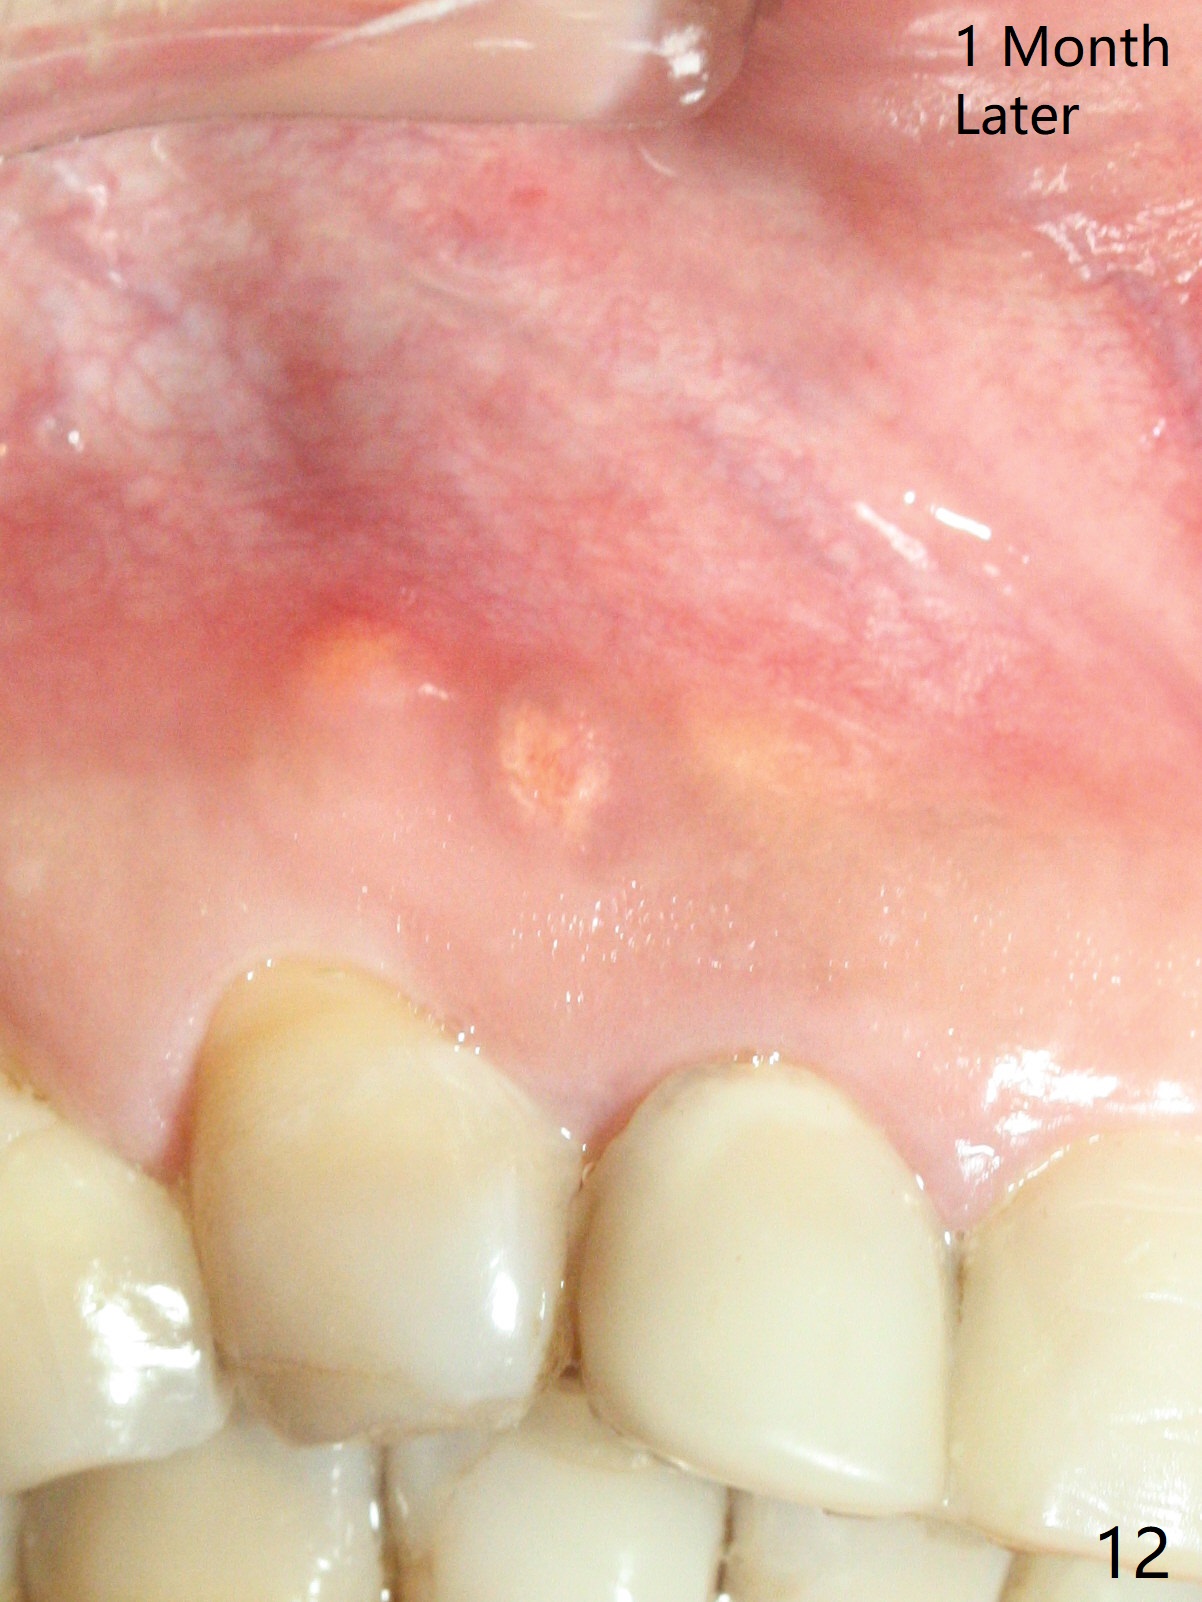

A 47-year-old woman (dental phobic) presented to clinic 9.5 years ago with periapical radiolucency (PARL) at #7 and 9 (Fig.1). RCT was done at #9 because of fistula and symptom 6 months later (Fig.2). While PARL increases at #7 without symptom, that at #9 disappears 8.5 years postop. Three months later, the patient returns for #7 RCT because of the abscesses (Fig.4 *) and pain. Intraop PA is taken with a 30/.06 rotary file in the canal with 19 mm working length (Fig.5). After use of #15 hand file for 20 mm, Ca(OH)2 paste is applied in the canal. When the rubber dam is removed, the abscesses enlarge (Fig.6), which may be related to sodium hypochlorite leakage. A dental explorer is used to try to find a bony opening to the large PARL without success (Fig.7). A postop PA reveals the leakage of Ca(OH)2 paste (Fig.8). Review of the preop PA (Fig.3,9) and intraop PAs (Fig.5,10) shows possible apical resorption and open apical foramen, which is the basis for the paste leakage (Fig.8,11). Careful analysis (with magnification and room light off) of pre- and intra-op PAs should be able to avoid use of #15 hand file out of apical constriction and the complication. The abscess has receded 1 month later (Fig.12). The paste has been resorbed 1 month later (Fig.13). A 30/.06 Gutta Percha is inserted at 18.5 mm (Fig.14 vs. 30/.06 file at 19 mm, 15 file at 20 mm last visit). Fig.15 is the final PA after closure of the access with composite (Fig.15).